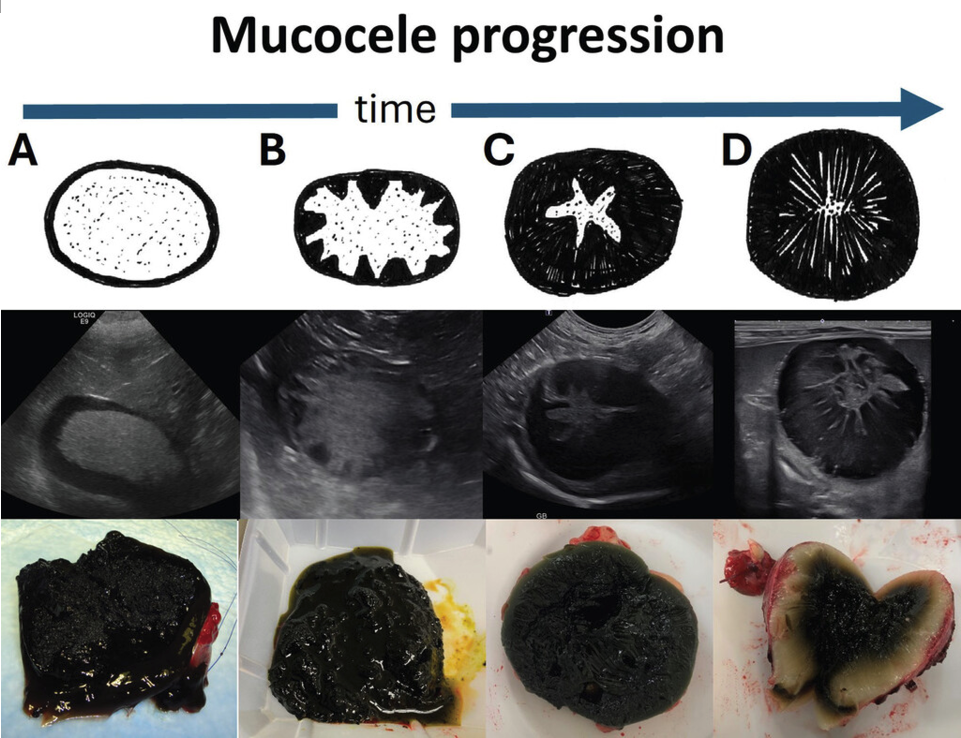

단순한 소화기 문제처럼 보이는 증상 이면에는 담낭 점액종이라는 위험한 원인이 숨어 있을 수 있습니다. 담낭 점액종은 초기 증상이 뚜렷하지 않아 ‘침묵의 질환’이라 불릴 만큼 발견이 늦어지는 경우가 많습니다.

질환이 진행되어 담낭이 과도하게 팽창하면, 담낭벽으로 가는 혈류가 줄어들어 담낭 괴사가 일어나거나 이차적인 세균 감염 및 담즙 배출 장애를 유발합니다. 이는 결국 전신 상태를 급격히 악화시키며 생명을 위협하는 응급 상황으로 이어질 수 있습니다.

Parkanzky MC, Grimes JA. Diagnosis and management of gallbladder mucocele formation in dogs. Vet Clin North Am Small Anim Pract. 2023;53(5):1109-1123. doi:10.1016/j.cvsm.2023.05.005